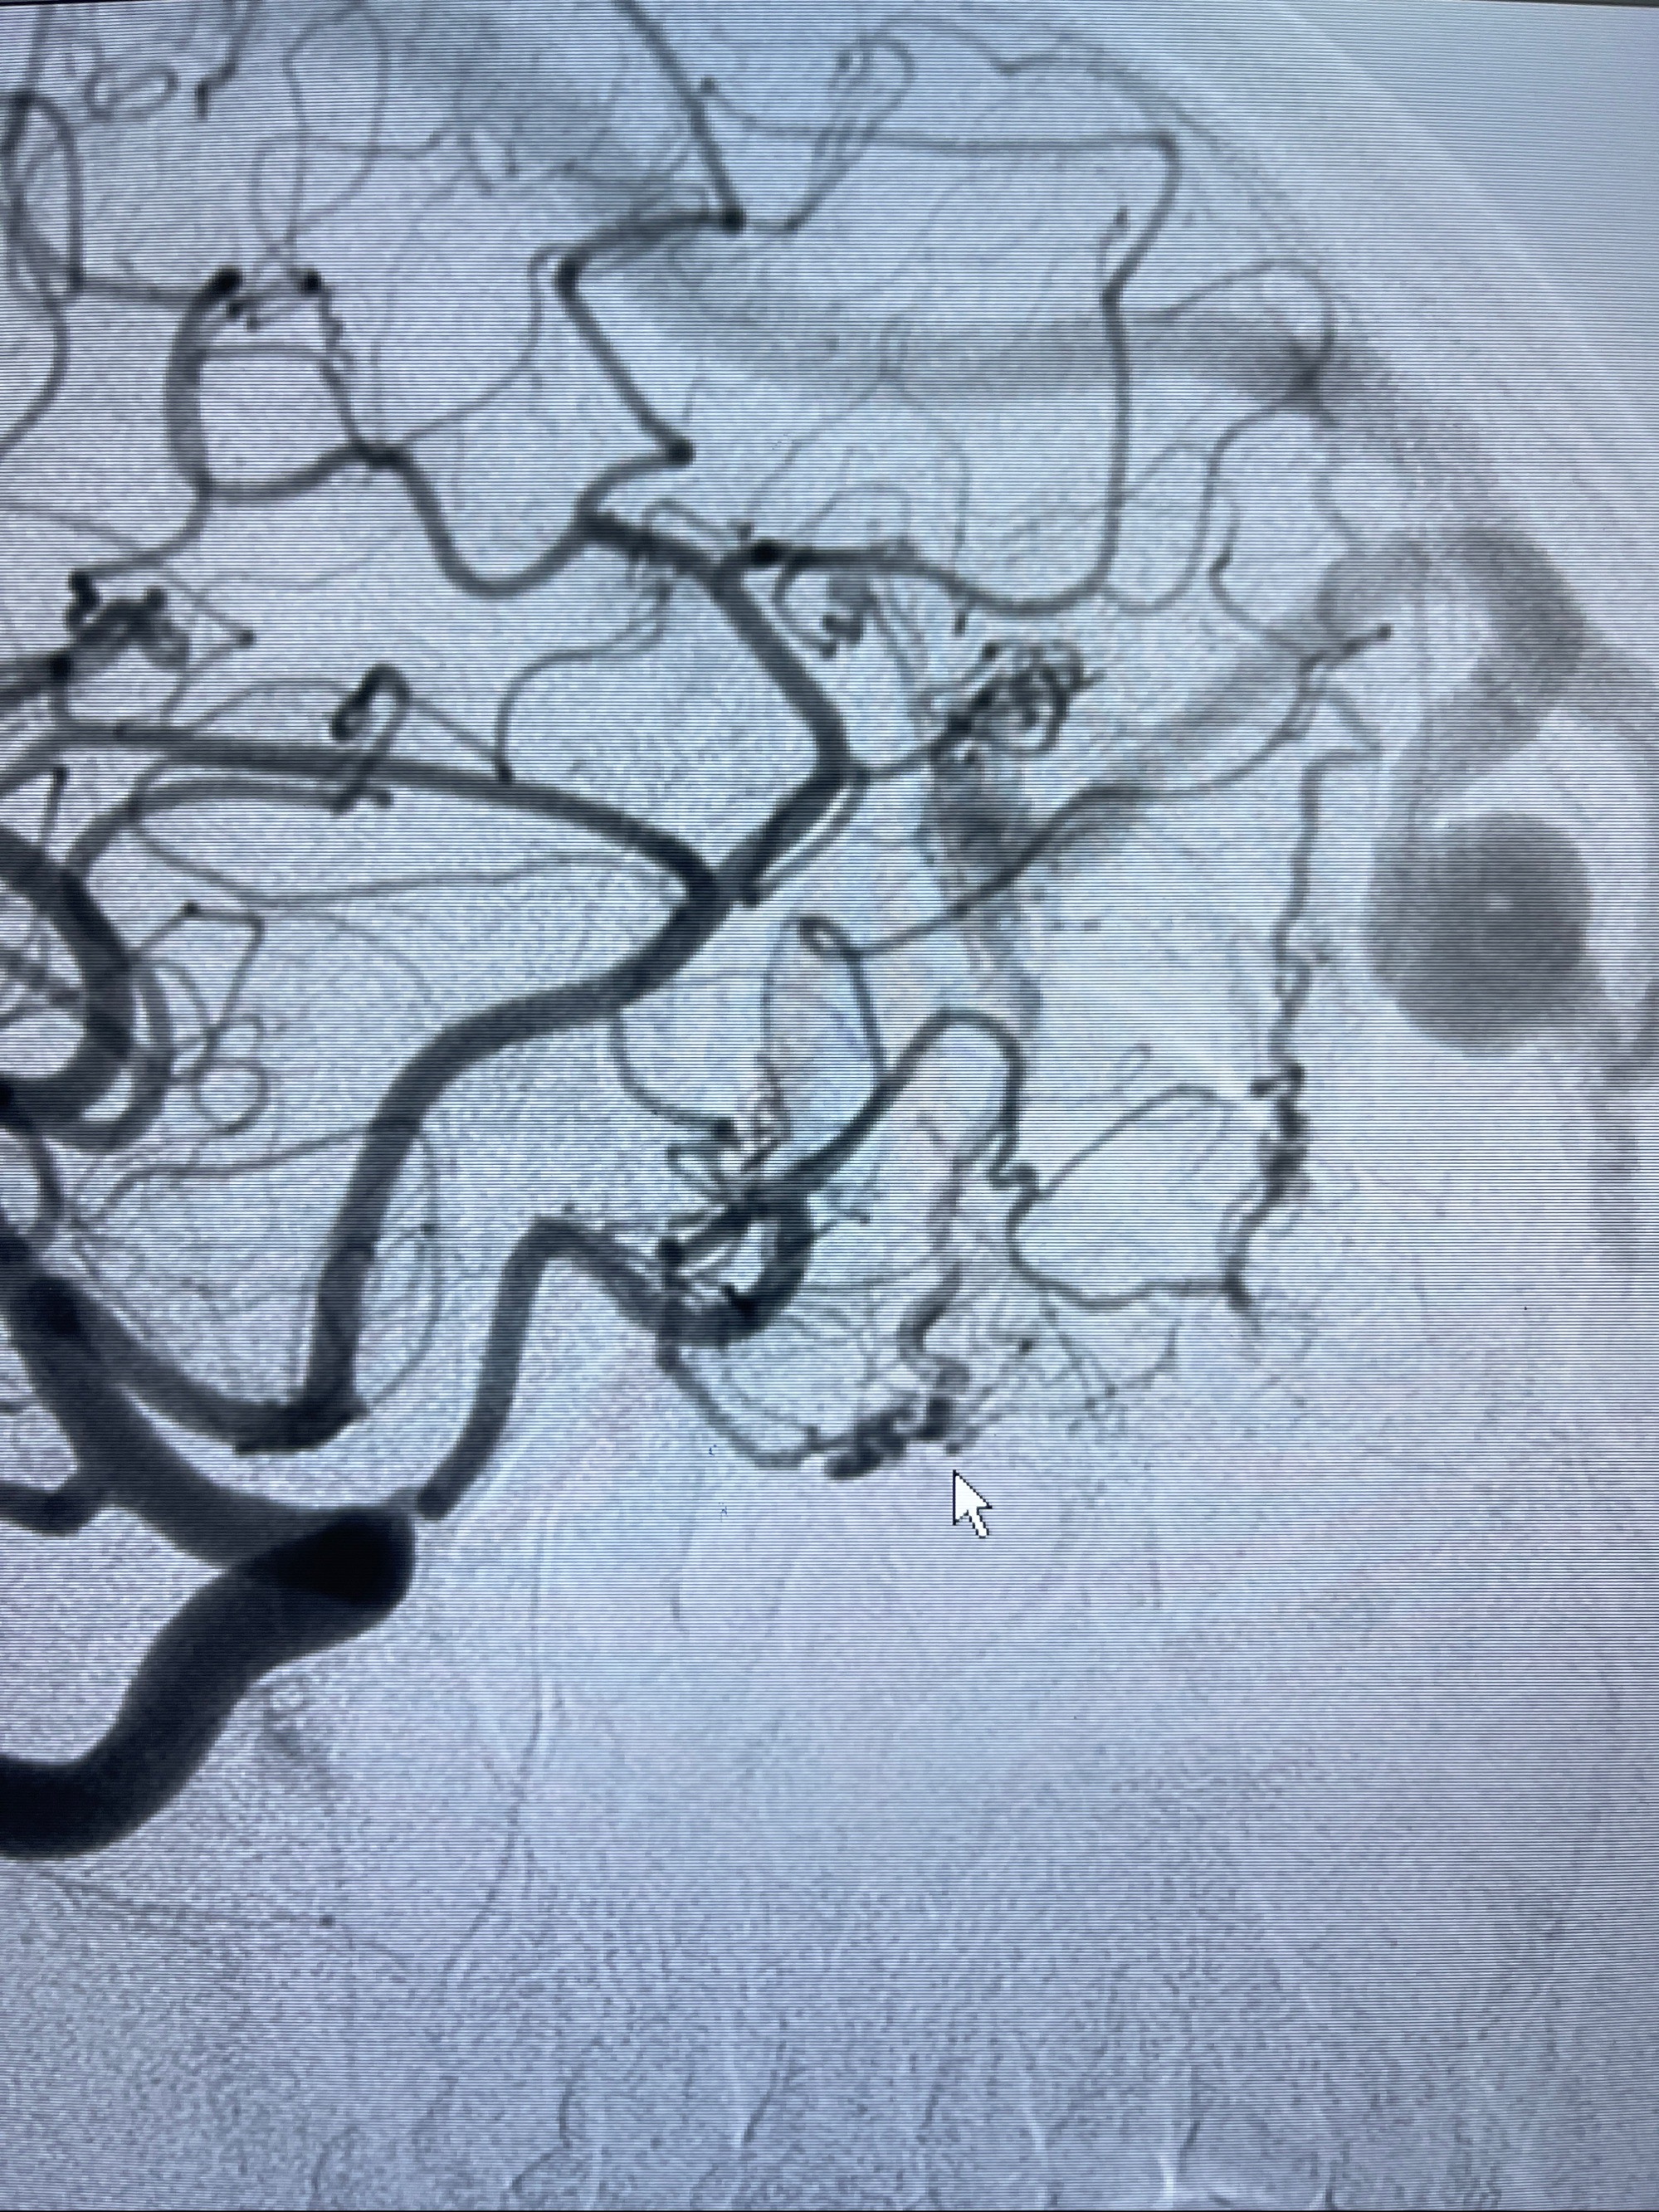

2023-09-13全脑血管造影:前颅底硬脑膜动静脉瘘,供血动脉为双侧胼周动脉、眼动脉脑膜支,静脉向上矢状窦方向引流